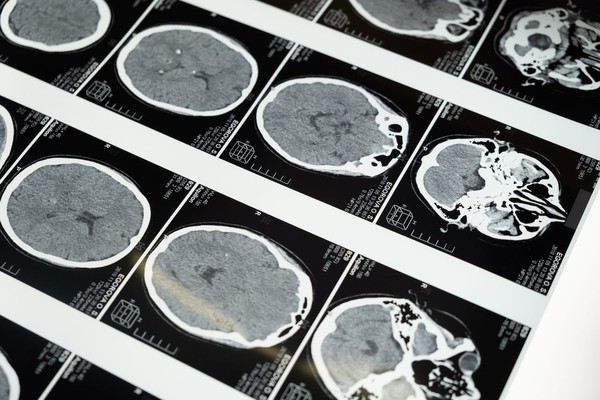

뇌졸중은 신경학적 검사, 뇌 CT, MRI 등 영상 검사를 통해 진단한다. 김한영 교수는 "뇌졸중은 시간과의 싸움"이라며 "뇌졸중 의심 증상이 나타나면 즉시 병원을 방문해 치료를 받는 것이 후유증을 최소화하는 가장 중요한 방법"이라고 강조했다.